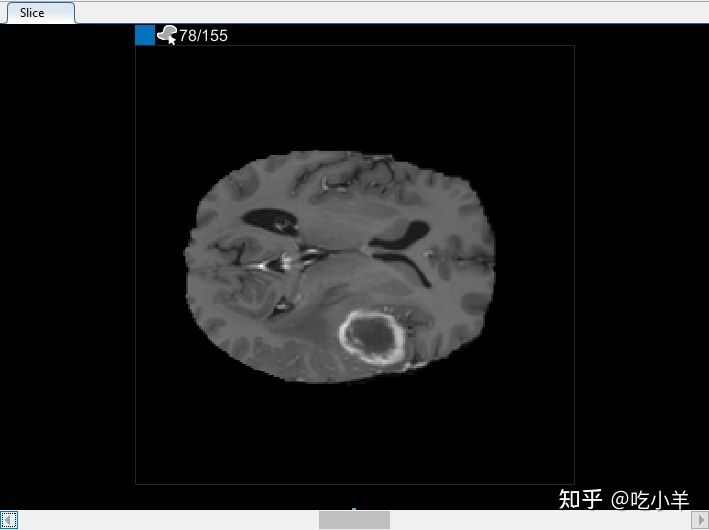

您还可以在“切片”窗格中查看体积的每个切片。使用窗格底部的滑块在切片之间移动。您可以在切片 35 到切片 88 上看到肿瘤。默认情况下,切片窗格显示沿 XY 轴定向的体积,但您可以使用分割器选项卡上工具条的方向部分中的按钮更改此设置。该切片窗格也是您使用绘图工具来定义的面具。